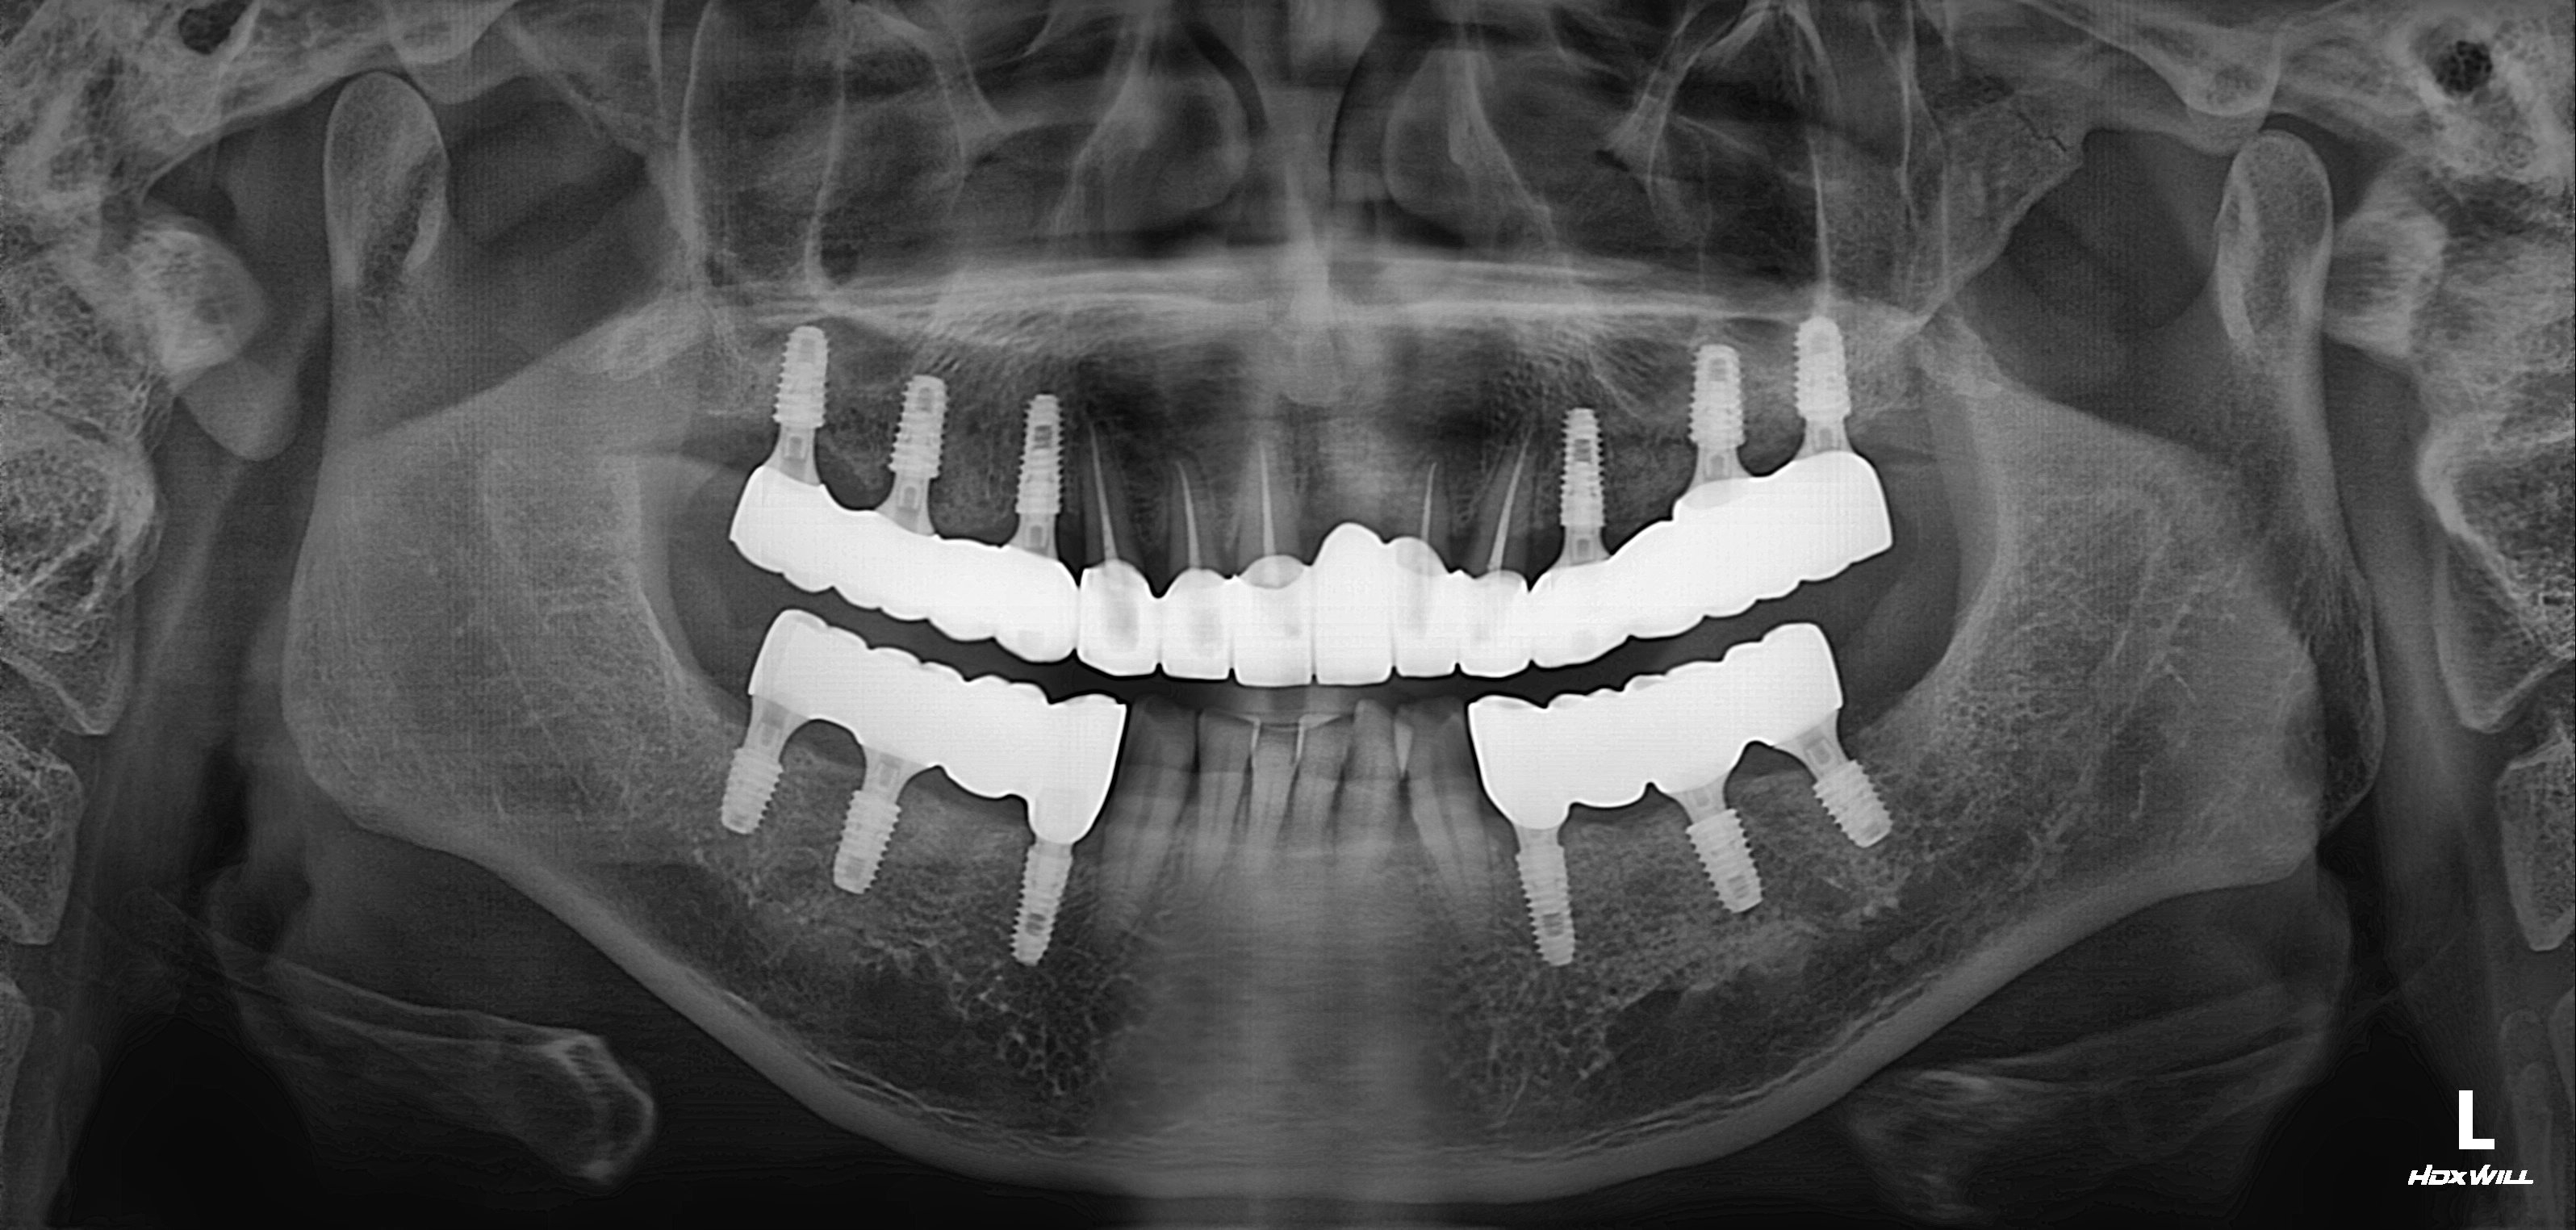

구치부 임플란트 식립사례

전후사진

수술 전

수술 후